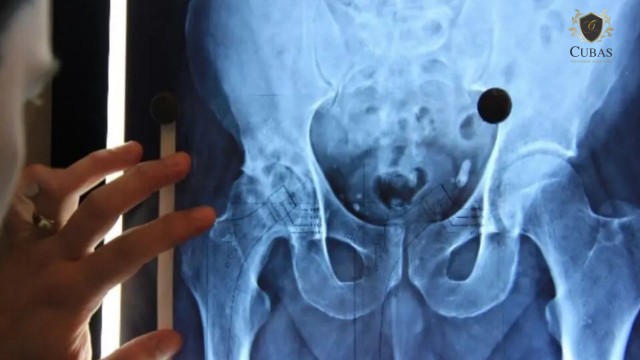

O autor narrou que realizou artroplastia total de quadril bilateral, em 2007, com implante de duas próteses. Sustentou que, a partir de 2019, voltou a sofrer com dores e perda parcial da capacidade de locomoção, ocasião em que foi constatada a soltura da prótese e a necessidade de revisão por meio de cirurgia. Ele afirmou que segue à espera do procedimento, tendo agravamento em seu quadro clínico.

O magistrado identificou que a artoplastia de quadril, cirurgia demandada pelo autor, consta na tabela de procedimentos do SUS. Ele levou em consideração o parecer feito pelo Telessaúde que apontou que o procedimento é considerado eletivo.